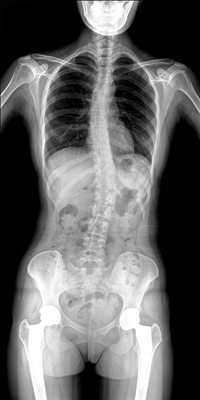

臨床需要對患者的脊柱情況有全面了解,故而術(shù)前術(shù)后均需要均需要借助DR拍攝X光片便于分析病情、明確診斷及術(shù)后觀察治療效果。大視野動態(tài)DR可以對患者的脊柱進行長尺寸攝影,一次拍攝就能獲取完整的脊柱全景圖像。診斷醫(yī)生通過拍攝后的影像測量全脊柱的生物角度、Cobb角等,為脊柱側(cè)彎的畸形矯正患者術(shù)前術(shù)后的檢查提供重要的診斷依據(jù)。

通過大視野動態(tài)DR進行全脊柱攝片,其得到的影像密度均勻、清晰、接緣處過渡自然。且操作更加便捷,不需要二次攝片然后進行圖像拼接,拍攝時間短,效率高。在減少輻射劑量的同時也能為臨床醫(yī)生帶來更精確的診斷信息。非拼接影像可保證雙腿測量(如力線)數(shù)據(jù)的準確性,有效避免攝影信息的丟失。給手術(shù)醫(yī)生提供準確的術(shù)前診斷數(shù)據(jù),提高手術(shù)成功率。

綜上所述,大視野動態(tài)DR進行全脊柱成像能夠清晰的呈現(xiàn)骨關(guān)節(jié)結(jié)構(gòu),可以在全景脊柱圖像基礎(chǔ)上對角度值進行測量,能夠很好的反映骨骼的真實比例與長度,為臨床診斷和治療提供了更精確的數(shù)據(jù),有著重要臨床應(yīng)用價值。